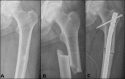

Atypical femoral fractures (AFFs) are uncommon and have been associated particularly with long-term antiresorptive therapy, including bisphosphonates. Although the pathogenesis of AFFs is unknown, their identification in bisphosphonate-naïve individuals and in monogenetic bone disorders has led to the hypothesis that genetic factors predispose to AFF. Our aim was to review and summarize the evidence for genetic factors in individuals with AFF. We conducted structured literature searches and hand-searching of conference abstracts/reference lists for key words relating to AFF and identified 2566 citations. Two individuals independently reviewed citations for (i) cases of AFF in monogenetic bone diseases and (ii) genetic studies in individuals with AFF. AFFs were reported in 23 individuals with the following 7 monogenetic bone disorders (gene): osteogenesis imperfecta (COL1A1/COL1A2), pycnodysostosis (CTSK), hypophosphatasia (ALPL), X-linked osteoporosis (PLS3), osteopetrosis, X-linked hypophosphatemia (PHEX), and osteoporosis pseudoglioma syndrome (LRP5). In 8 cases (35%), the monogenetic bone disorder was uncovered after the AFF occurred. Cases of bisphosphonate-naïve AFF were reported in pycnodysostosis, hypophosphatasia, osteopetrosis, X-linked hypophosphatemia, and osteoporosis pseudoglioma syndrome. A pilot study in 13 AFF patients and 268 controls identified a greater number of rare variants in AFF cases using exon array analysis. A whole-exome sequencing study in 3 sisters with AFFs showed, among 37 shared genetic variants, a p.Asp188Tyr mutation in the GGPS1 gene in the mevalonate pathway, critical to osteoclast function, which is also inhibited by bisphosphonates. Two studies completed targeted ALPL gene sequencing, an ALPL heterozygous mutation was found in 1 case of a cohort of 11 AFFs, whereas the second study comprising 10 AFF cases did not find mutations in ALPL. Targeted sequencing of ALPL, COL1A1, COL1A2, and SOX9 genes in 5 cases of AFF identified a variant in COL1A2 in 1 case. These findings suggest a genetic susceptibility for AFFs. A large multicenter collaborative study of well-phenotyped AFF cases and controls is needed to understand the role of genetics in this uncommon condition.